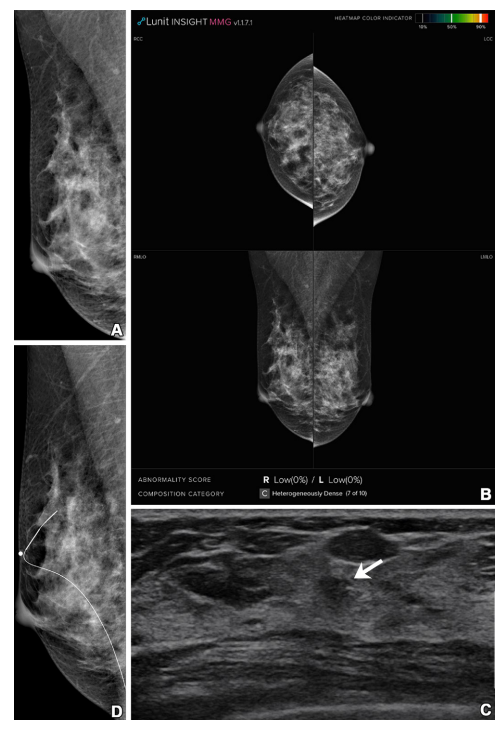

Figure 3: Imaging in a 41-year-old woman with heterogeneously dense breasts (Breast Imaging Reporting and Data System category c). (A, B) Right mediolateral oblique digital mammogram (A) and right and left craniocaudal (RCC, LCC) and right and left mediolateral oblique (RMLO, LMLO) mammograms with artificial intelligence (Lunit INSIGHT MMG, version 1.1.7.1; Lunit) (B) show no abnormality. (C) Supplemental transverse US image shows a 1.0-cm irregular mass (arrow) in the right breast. (D) Right mediolateral oblique digital mammogram after US-guided wire localization shows no suspicious findings, even in retrospect. The radiopaque round marker, which is attached on the skin to mark the wire insertion site, is visible. The patient was treated with breast-conserving surgery, and the mass was proven to be invasive ductal carcinoma (pT1N0, 0.7 cm in size, estrogen receptor and progesterone receptor positive, human epidermal growth factor receptor 2 negative, histologic grade 1).

图3: 影像显示一名41岁乳腺结构异质性致密的女性(乳腺影像报告与数据系统分类c)。(A, B) 右侧中斜位数字乳腺X线照片 (A) 和右侧及左侧头尾位 (RCC, LCC) 以及右侧及左侧中斜位 (RMLO, LMLO) 乳腺X线照片使用人工智能(Lunit INSIGHT MMG,版本1.1.7.1;Lunit)辅助 (B) 显示未见异常。(C) 补充横断面超声图像显示右乳房有一个1.0厘米的不规则肿块(箭头)。(D) 超声引导下的导丝定位后的右侧中斜位数字乳腺X线照片在回顾时仍未显示可疑发现。附着在皮肤上的不透明圆形标记可见,用于标记导丝插入部位。患者接受了乳腺保留手术,肿块被证实为浸润性导管癌(pT1N0,大小0.7厘米,雌激素受体和孕激素受体阳性,HER2阴性,组织学等级为1)。